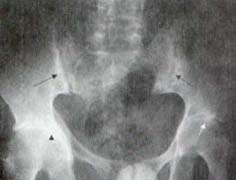

La espondilitis anquilosante es una enfermedad inflamatoria crónica de causa desconocida que afecta principalmente el esqueleto axial. Es una patología de adultos jóvenes que afecta con mayor frecuencia a los hombres, en una relación de 3:1 y la enfermedad progresa más lentamente en las mujeres desde el punto de vista clínico y radiológico1. Existen alteraciones en las articulaciones sinoviales y cartilaginosas y en las zonas de inserción de tendones y ligamentos en el hueso (entesis), tanto en la columna como en otras localizaciones. Lo característico de esta enfermedad es la sacroilitis, que típicamente es bilateral y simétrica (Figura 4).

Figura 4. Radiografía de Pelvis. Sacroilitis bilateral. Seudo – ensanchamiento de las articulaciones sacroilíacas,

con irregularidad en los bordes y esclerosis subcondral (Flechas negras).

También se aprecia el compromiso bilateral de caderas

(Flecha Blanca y cabeza de flecha).